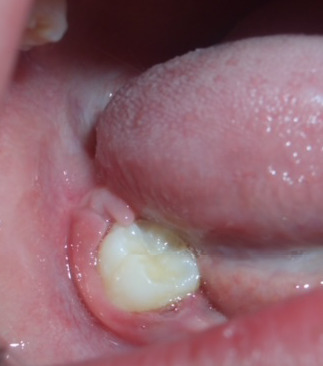

Materials and method: Clinical and radiographic examinations were used to evaluate 95 patients diagnosed with LCH, aged 0 to 16 years, who were referred to the Department of Comprehensive Pediatric Dentistry at the School of Dentistry, University of Buenos Aires. Clinical histories were prepared and informed consents obtained. Lesions were diagnosed by observation, palpation and biopsies, and grouped according to affected tissues into bone, mucosal, and bone-mucosal.

Results: 42.1% presented oral lesions, and in 14.73%, these lesions were the first manifestation of LCH. Ninety percent presented only bone lesions, while the remaining 10% presented bone-mucosal and mucosal lesions. In the single-system subtype, 52.5% presented bone lesions. In the multisystem subtypes (with or without risk organs), all three types of lesions were found. The association between age at which LCH was diagnosed and oral tissue involvement showed that bone-mucosal lesions occur in young children (average age 1.4 years) diagnosed with multisystem LCH. Oral mucosa was only affected in reactivations of the disease.

Conclusions: A high frequency of oral lesions was observed, which were sometimes the first manifestation of the disease, most often affecting bone tissue. Dentists can play an active role in the initial diagnosis of the disease.